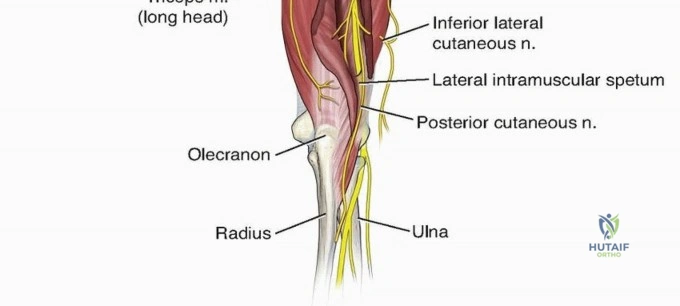

From the triangular interval, the radial nerve transverses from medial to lateral along the posterior aspect of the humeral shaft within the spiral groove. It pierces the lateral intermuscular septum approximately 10 to 12 centimeters proximal to the lateral epicondyle to enter the anterior compartment of the arm. Distally, the nerve travels in the anatomic interval between the brachialis muscle medially and the brachioradialis muscle laterally. This specific interval is the foundation of the distal anterolateral approach to the humerus.

For distal third fractures, the exposure must transition to the interval between the brachialis and the brachioradialis. The radial nerve emerges from the posterior compartment by piercing the lateral intermuscular septum and travels distally in the cleft between the brachialis (medially) and the brachioradialis (laterally).

To safely exploit this interval, the fascia between the brachialis and brachioradialis is carefully incised. The radial nerve must be actively identified and protected. It is often easiest to identify the nerve distally where the interval is wider and trace it proximally to where it pierces the septum. Once identified, the nerve is gently mobilized and protected with vessel loops. Retraction of the nerve must be minimal and meticulous to prevent iatrogenic neuropraxia.